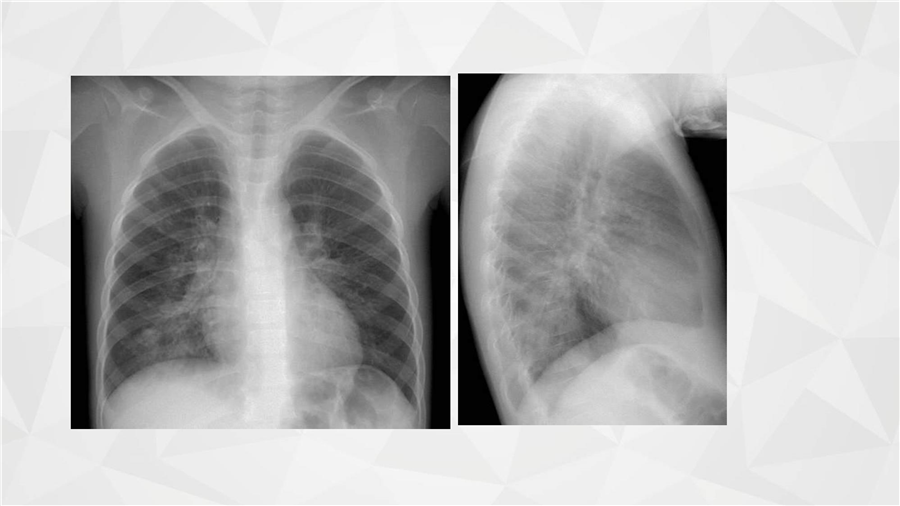

呼吸系统三